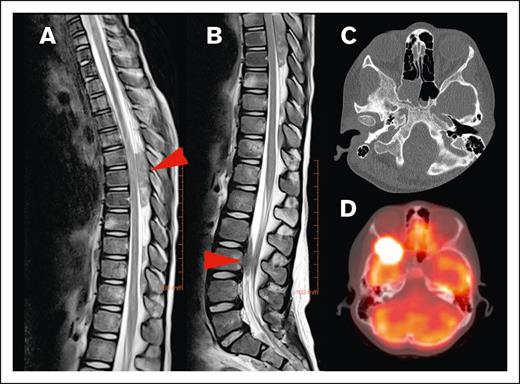

None of the lesions involved the intra-axial CNS space. All lesions extended into the extra-axial CNS space from surrounding tissue. At the time of diagnosis, the majority of patients (82.2%) had a single lesion involving the CNS, whereas 4.4% had up to 3 discrete lesions in the CNS. The lesions extended into the thoracic spine (45.5%), sacrum (23.6%), lumbar spine (21.8%), cervical spine (5.5%), and skull (3.6%; Figure 2). In our cohort, 45% of lesions originated from adjacent bone and 40% from adjacent soft tissue. We were unable to determine the tissue of origin for 15% of lesions (Figure 3).

Figure 2.

Locations of HL CNS involvement. (A) Tumor in the dorsal part of the thoracic spinal canal and (B) ventral part of the lumbar spine (T2-weighted MRI sequences of the same patient, red arrow indicating tumor location), (C) tumor originating from the skull (bone window with subtle osteolysis, and (D) PET-fusion demonstrating the same lesion as in panel C extending into orbit and middle cranial fossa.